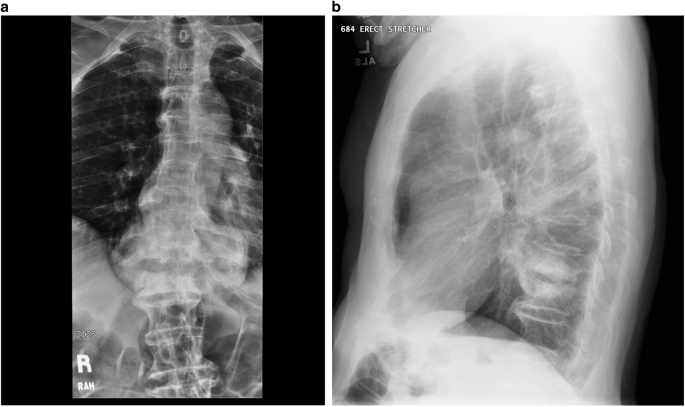

Retrolisthesis and pseudarthrosis image This image illustrates retrolisthesis and pseudarthrosis.